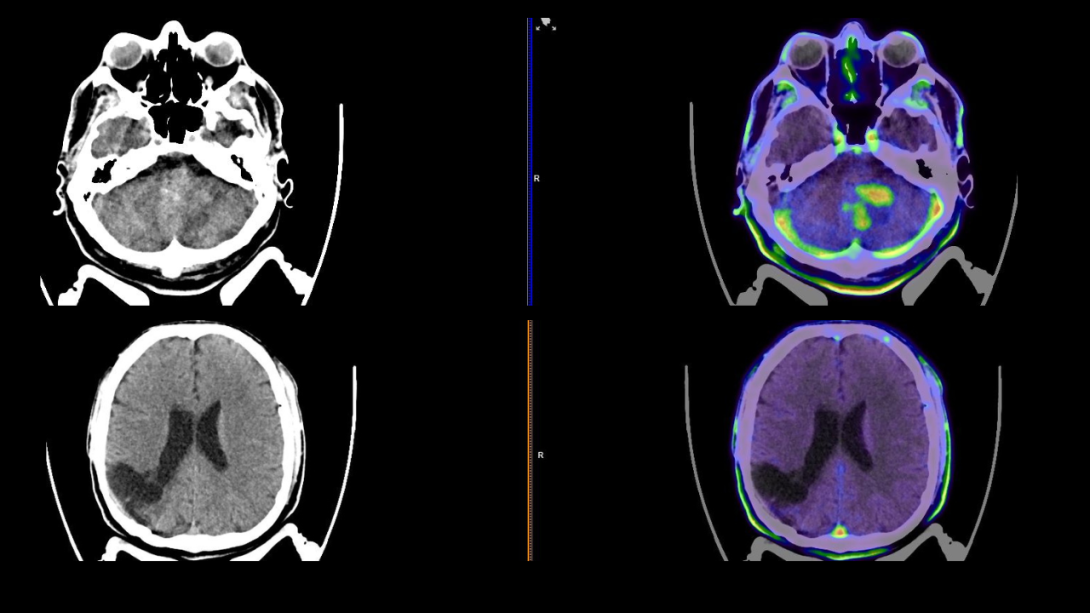

La Clínica del Country realizó en Bogotá el primer estudio PET-F18 FET y PET-DOPA, mejorando diagnósticos en tumores cerebrales y Parkinson.

La Clínica del Country marcó un hito en la medicina nuclear con la realización del primer estudio PET-F18 FET (Fluoroetiltirosina), una herramienta innovadora que permite diagnósticos más precisos en tumores cerebrales, especialmente glioblastomas. El procedimiento fue desarrollado por el equipo de Medicina Nuclear de la Clínica del Country, posicionando a la institución como referente en innovación médica.

El PET-F18 FET utiliza un aminoácido radiomarcado que se concentra en lesiones cerebrales y diferencia entre células normales y malignas. Esta técnica permite identificar si una lesión es benigna o maligna, confirmar recaídas tumorales y planificar biopsias o radioterapias.

“El FET nunca se había hecho en ningún centro de Bogotá. Su valor radica en que nos ayuda a saber si una lesión es benigna o maligna, si hay recaída tumoral o solo secuelas por radioterapia”, explicó Gerardo Cortés, jefe de Medicina Nuclear de la Clínica del Country.